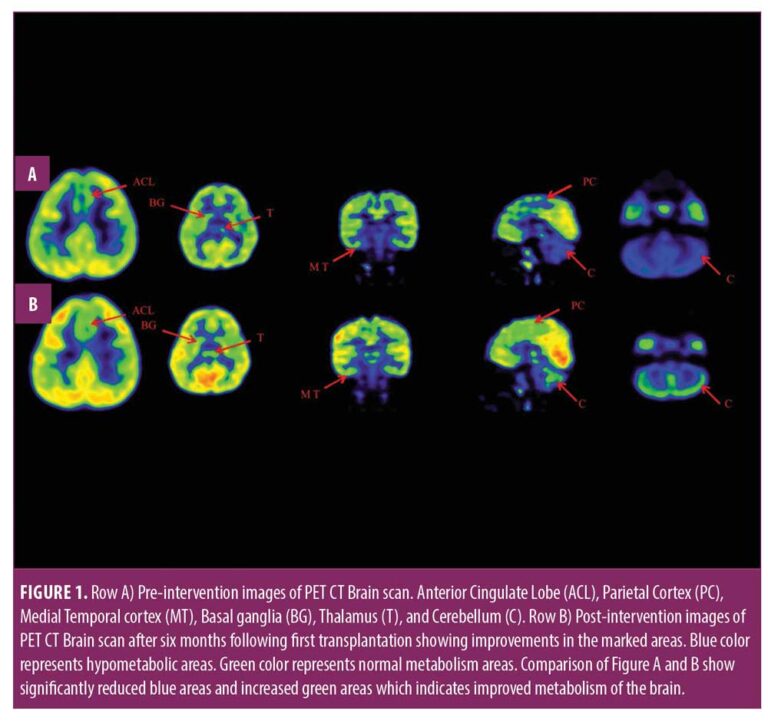

在認(rèn)知上,由于他定期上學(xué),他的注意力持續(xù)時(shí)間和坐姿耐受力也得到了改善。GMFM分?jǐn)?shù)從60.67提高到67。GMFCS等級(jí)由3級(jí)提升至2級(jí);FIM評(píng)分從97分提高到99分。比較第一次細(xì)胞治療之前和之后7個(gè)月期間進(jìn)行的腦部PET CT掃描結(jié)果,發(fā)現(xiàn)前扣帶回葉、頂葉皮層、內(nèi)側(cè)顳葉皮層、丘腦、基底神經(jīng)節(jié)和小腦(表1)。

這項(xiàng)研究表明,多種干細(xì)胞療法結(jié)合神經(jīng)康復(fù)可有效改善腦癱患者的粗大運(yùn)動(dòng)功能和功能獨(dú)立性。自體BMMNC多次移植后進(jìn)行強(qiáng)烈的神經(jīng)康復(fù)可加快神經(jīng)再生過程,這反過來又反映了患者殘疾程度和生活質(zhì)量的積極結(jié)果。PET CT掃描可以有效地用于監(jiān)測(cè)干預(yù)后細(xì)胞水平發(fā)生的變化。因此,多細(xì)胞療法是安全、可行的,并且可以有效地與腦癱的神經(jīng)康復(fù)相結(jié)合作為增強(qiáng)治療。